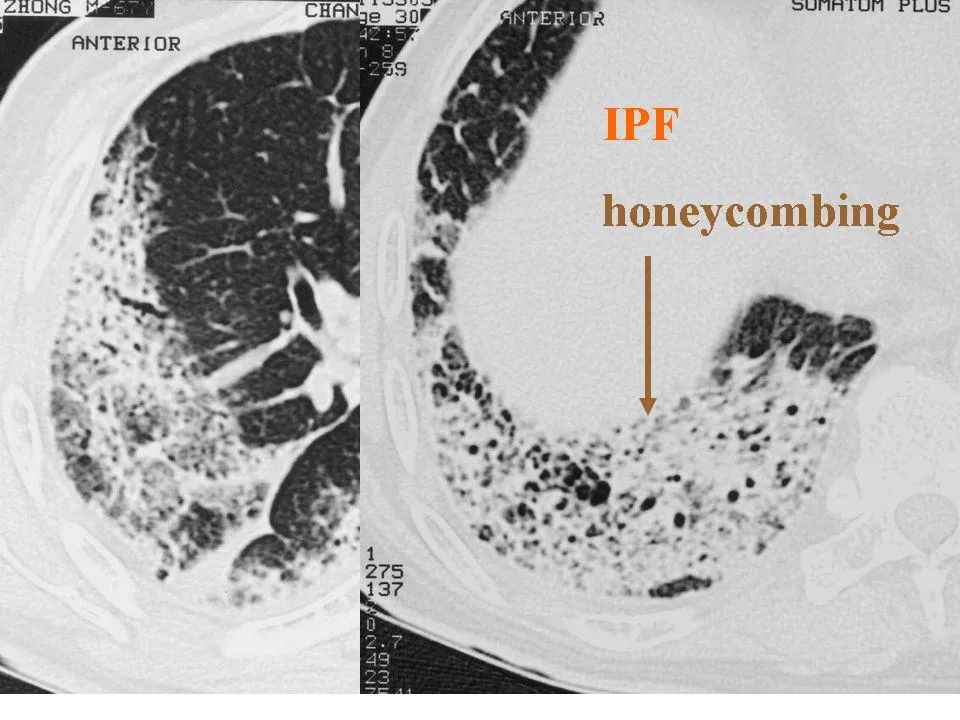

细支气管肺泡癌的影像学

图片尺寸960x720

细支气管肺泡癌的影像学_李惠民